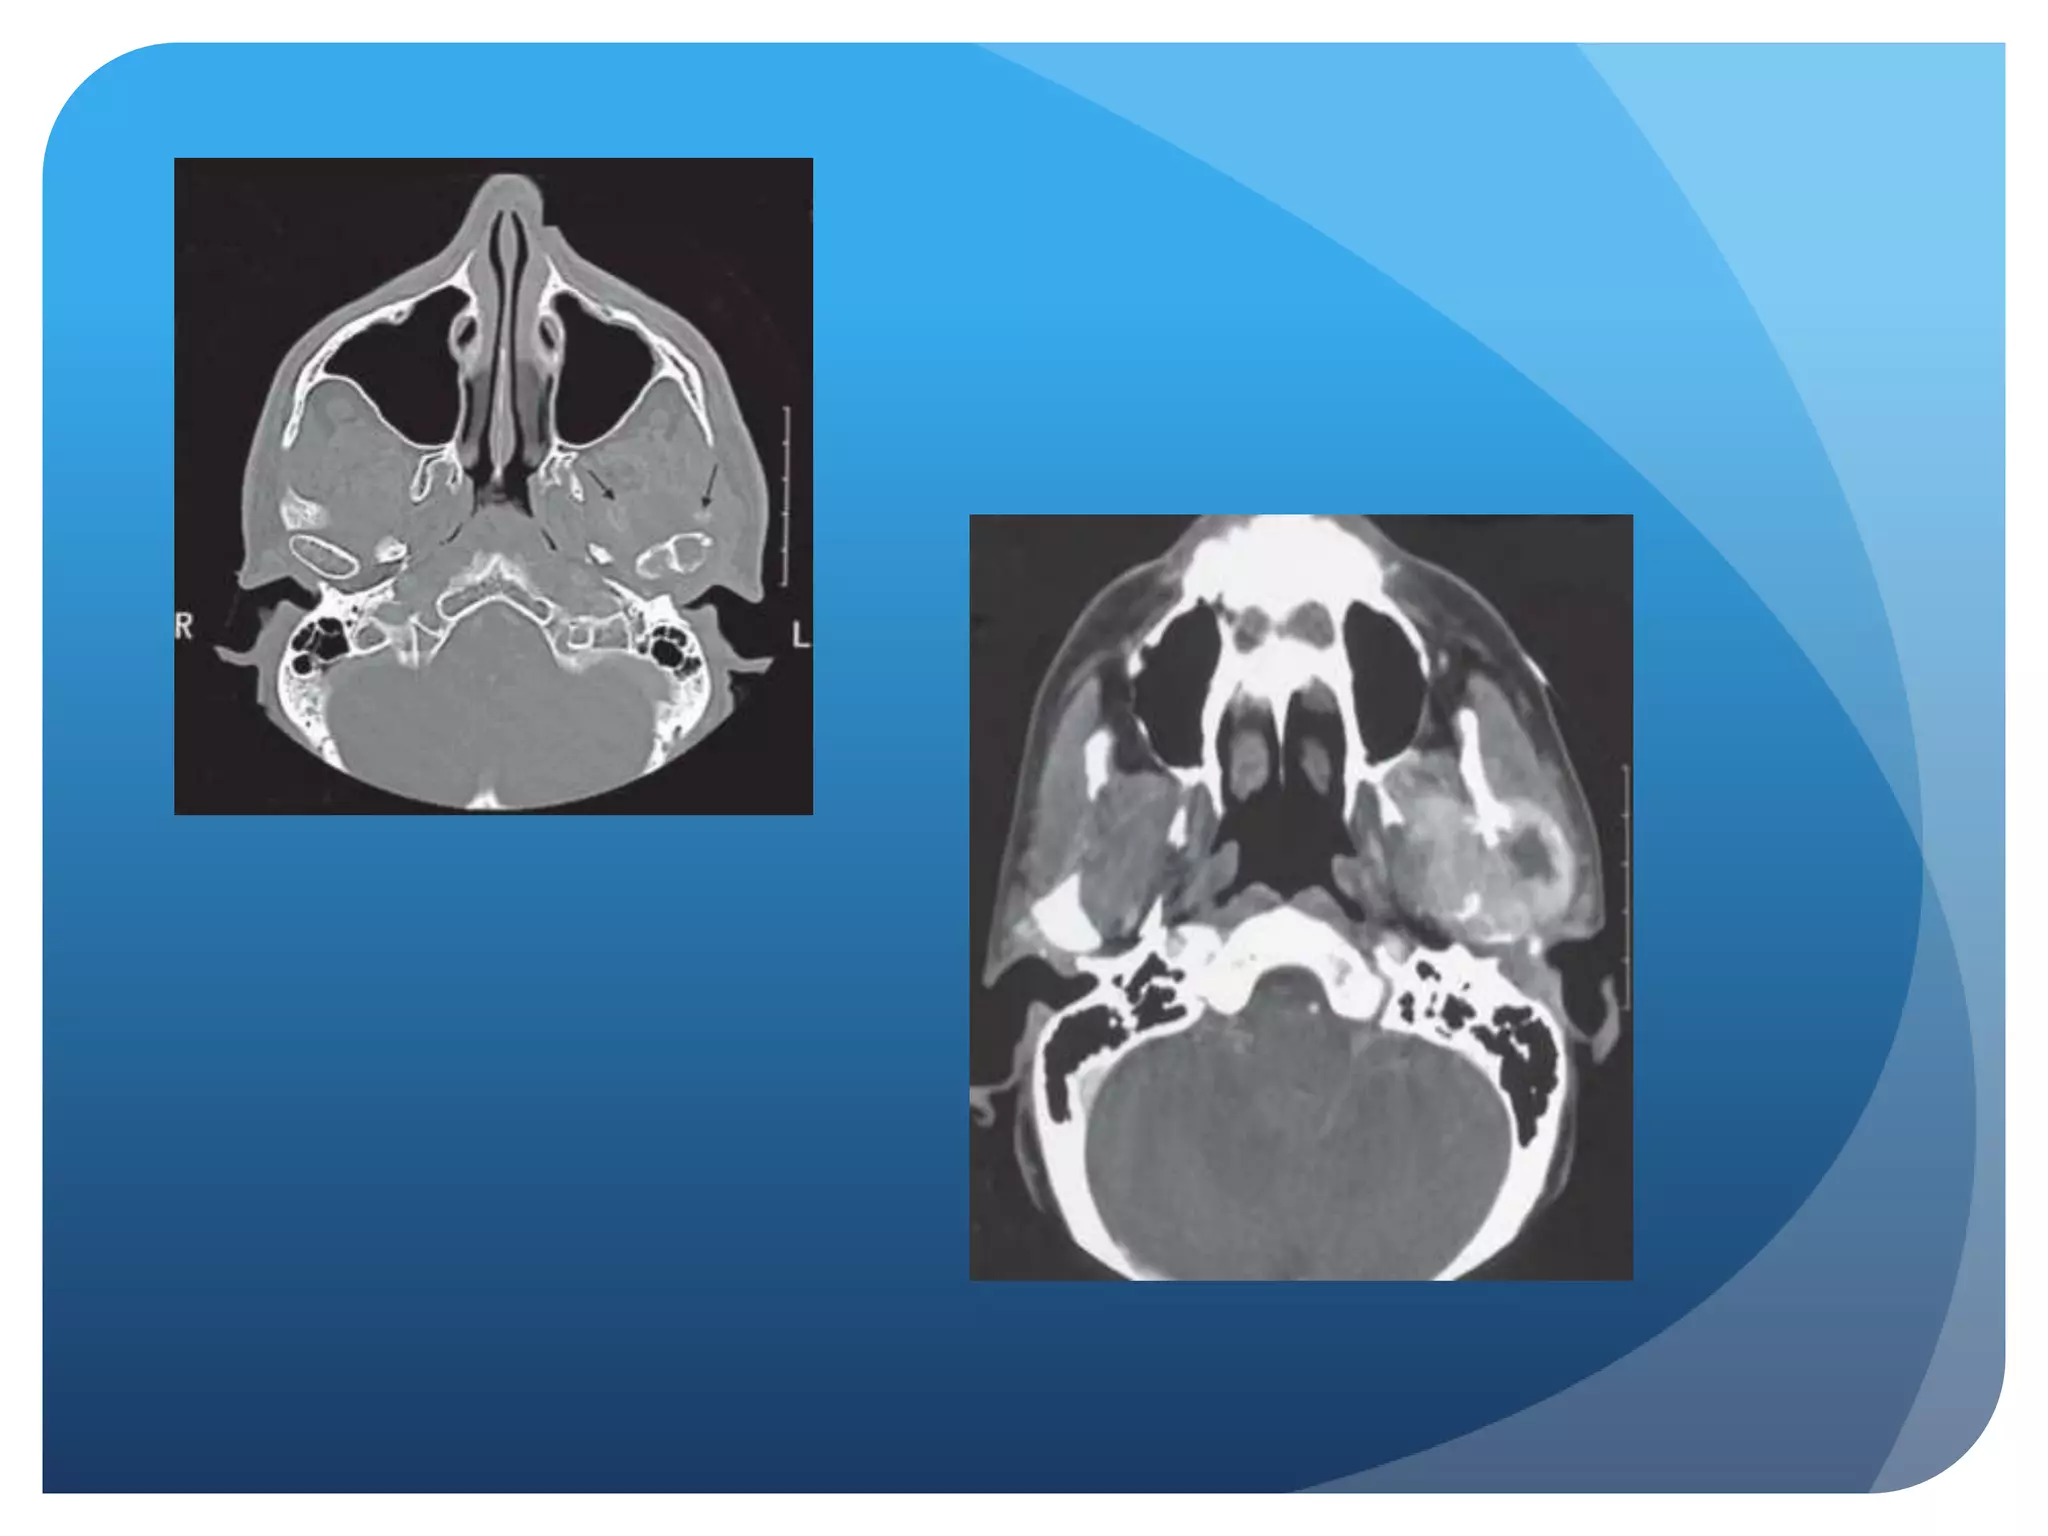

• #38 CT axial image bone algorithm. Note the calcifications anterior to the right condyle and large erosions involving the medial pole of the condyle.

• #45 Right condyle and ramus are markedly enlarged